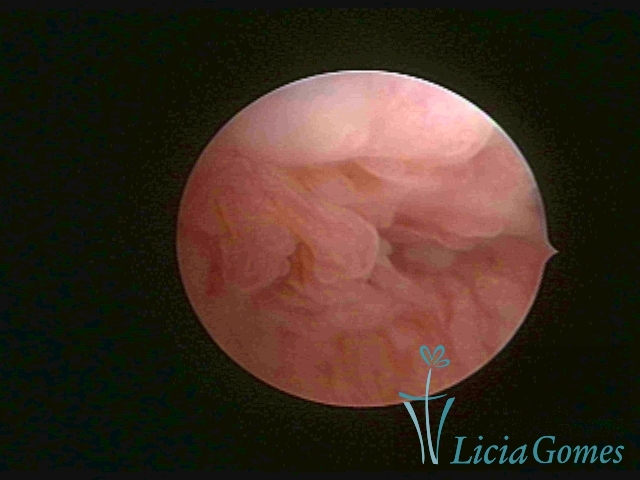

Terceira porção ou porção superior

Apresenta a mucosa com a superfície lisa e pouco vascularizada até a altura do orifício interno